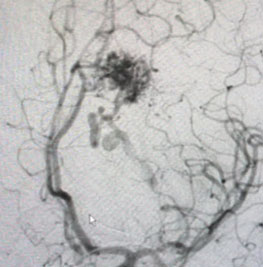

Angiogram (Figure 3 and 4) confirmed the presence of a deep left frontal AVM without any associated aneurysms.

Fig. 3

Fig. 4